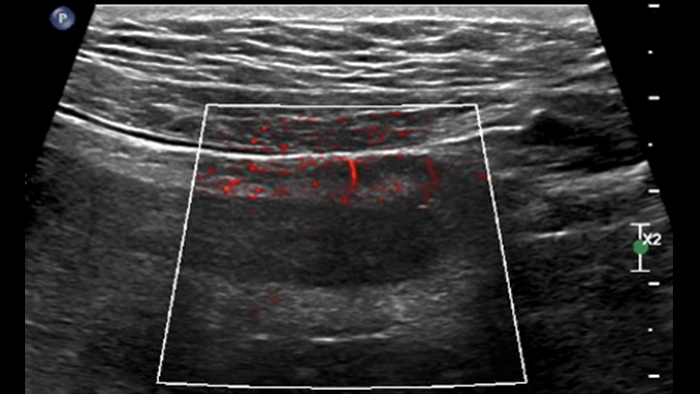

Ces images précises des lésions des couches pariétales forment la base de l’interprétation des changements induits par l’inflammation des parois intestinales et par conséquent de la différenciation entre la maladie de Crohn et la rectocolite hémorragique. L’exploration avec la technologie MFI (MicroFlow Imaging) constitue la deuxième étape. Il s’agit de reconnaître l’aspect de l’hypervascularisation induite par des épisodes inflammatoires actifs. La paroi intestinale normale semble comporter peu de microvaisseaux détectables, uniquement à l’interface de la muqueuse et de la sous-muqueuse, et dans le tissu adipeux mésentérique adjacent. Inversement, la paroi inflammatoire présente de nombreux microvaisseaux. La distinction entre les images d’artefacts de mouvement et les microvaisseaux circulants est alors un point essentiel nécessitant un ajustement parfait des paramètres de détection des micro-flux (voir les boucles, diapositive 8). La comparaison des 4 images suivantes de la maladie de Crohn met en évidence des différences claires qui devraient être interprétées comme étant représentatives des différents états inflammatoires. L’image 1 ne comporte aucun vaisseau visible, ce qui correspond probablement à une absence d’activité. L’image 2 présente quelques vaisseaux ; nous pouvons en conclure que cela correspond à une activité modérée. L’image 3 comporte un plus grand nombre de vaisseaux, signe probable d’une activité intense. L’image 4 présente encore plus de vaisseaux de type pulsatile, ce qui évoque probablement une activité très intense.

Dans le cas de la forme aiguë de la rectocolite hémorragique, la technologie MFI met en évidence un grand nombre de vaisseaux dans la paroi, mais également dans le tissu adipeux adjacent. Dans le cas des pseudopolypes, des vaisseaux peuvent parfois s’y développer.

Est-ce si simple ? Probablement pas car 2 questions importantes restent en suspens : Les paramètres d’acquisition MFI doivent donc être adaptés à la réduction des artefacts sans masquer le micro-flux des vaisseaux. Les deux images suivantes de la même paroi intestinale sont obtenues avec des paramètres différents en termes de sensibilité du micro-flux et de détection de la vélocité. Après ajustement des paramètres, la deuxième image permet apparemment d’effacer les artefacts de mouvement (petites taches) tout en laissant les microvaisseaux pariétaux (images linéaires) clairement visibles. Il semble que cet ajustement ne soit pas toujours facile à obtenir pour valider la signification des images de micro-circulation de flux, et donc la densité des microvaisseaux, qui constitue l’information principale pour détecter une inflammation aiguë.